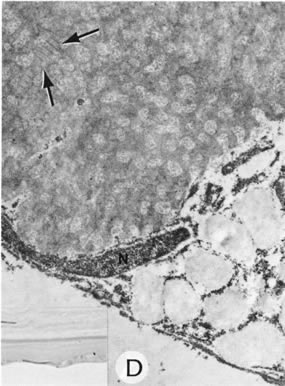

PETERS' ANOMALY

Peters' anomaly includes absence of central corneal endothelium, Descemet's membrane, and variable amounts of corneal stroma (Fig. 4). In most cases Bowman's membrane also is absent. Peters' anomaly may be caused by primary dysgenesis of the corneal endothelial mesoderm, primary dysgenesis of keratocyte and endothelial neural crest mesoderm, or secondary endothelial degeneration due to late anterior displacement of a normally developed crystalline lens.48 In addition, it has been suggested that abnormal apposition of an ectopic lens to the developing cornea during the second or third month of gestation may be the cause of exceptional cases of peripheral Peters' anomaly.49

Fig. 4. Peters' anomaly. A. Note the central corneal scar in the right and left eyes. The lens was adherent to the back of the corneal scar. Iris abnormalities also were present. B. The anterior segment shows a posterior corneal defect, a “top hat” appearance of the lens, and total adherence of the anterior surface of the iris to the cornea. C. High magnification shows termination of the endothelium and Descemet's membrane (arrow), corneal thinning, and localized absence of Bowman's membrane. The lens (lower left) is artifactually separated from the cornea. D. A PAS-positive membrane (lens capsule) is shown (top) adherent to the posterior corneal surface (arrow). The lens cortex (c) is artifactually separated from the rest of the lens (bottom). (Courtesy of SEI Photoarchives.) (B–D modified from Scheie HG, Yanoff M: Peter's anomaly and total posterior coloboma of retinal pigment epithelium and choroid. Arch Ophthalmol 87:525, 1972.)

Histopathologic findings include absence of Descemet's membrane, corneal endothelium, and usually Bowman's membrane, as well as thinning of corneal stroma. The defects in Descemet's membrane, although usually single and central, may be multiple and isolated to the periphery or may be limited to an area of adhesion of iris.56 Descemet's membrane has been found to have embryonal ultrastructural characteristics combined with attenuated endothelium.57 The corneal stromal lamella are more irregular and closely packed when compared with normal. Immunohistochemical markers indicate that a normal complement of collagens type I, III, IV, V, and VI occurs in Peters' anomaly; however, an increased concentration may occur of the adhesive protein fibronectin, which is known to play a role in the embryologic development of the cornea.58–60